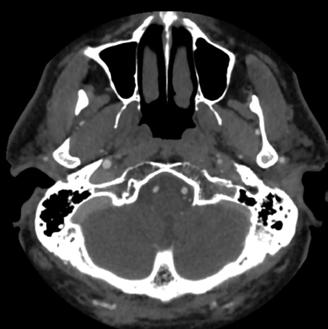

• Studiul opacifierii ramurilor corticale ale arterelor cerebrale medii (M4) drepte și stângi și a venelor cerebrale interne drepte și stângi (Fig.1).

Fig.1 ACTMS cranio-cerebrală, recon MIP în plan axial (a,b) și sagital (c): aspect normal; (a) opacifierea arterelor temporale dreaptă și stângă (săgeţi); (b) opaciferea ramurilor corticale ale arterelor cerebrale medii (M4)-săgeţi albe; opaciferea venelor cerebrale interne dreaptă și stângă (săgeţi negre-b și c).

Semiologie:

▶ Absența opacifierii M4 = 1 punct

▶ Opacifierea M4 = 0 punct

▶ Absența opacifierii venei cerebrale interne = 1 punct

▶ Opacifierea venei cerebrale interne = 0 puncte

• Un scor egal sau mai mare de 3 confirmă stopul circulator intracerebral. In acest caz, concluzia examinării este: „stop circulator intracerebral” care vine în sprijinul diagnosticului clinic de moarte cerebrală sau aspect ACT compatibil cu moartea cerebrală

• În caz contrar, concluzia examinării este „absența opririi circulatiei intracerebrale”, situaţie în care diagnosticul clinic de MC nu este confirmat.

În cazul opacifierii unilaterale a uneia dintre cele două artere cerebrale medii, diagnosticul de MC poate fi afirmată dacă este absentă opacifierea venelor cerebrale interne (Fig,2).